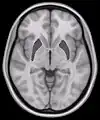

Coronal section of brain through intermediate mass of third ventricle. (Putamen labeled at top.)

This is a transverse section of the striatum from a structural MR image. The striatum includes the caudate nucleus (top) and putamen (right) and the globus pallidus (left).